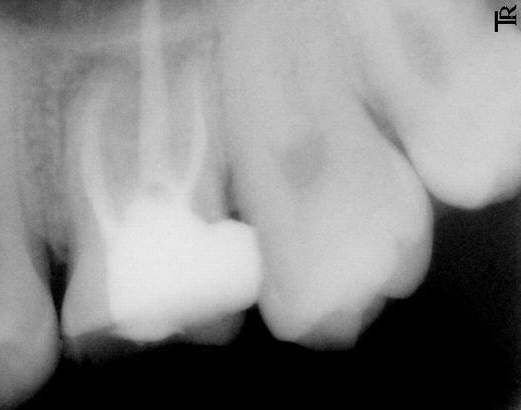

/art_img/200708/19_0133432466.jpg;这张是别人的,做过根管治疗的),而我的没有,很正常的根,不是白色的。现在三个月了,还是疼,特别是外刷时,但很奇怪,最近去换药时,不管他怎么用力去撬都不疼的,但如果深入地去捻的话就会很痛很痛哩,现在他给我封的药是fc+碘,不明白为什么。。。

>>>>>>>>休闲养生网回答:拍摄X线片,根管内没有白色的充填物,可以肯定根本没有根管充填.与根管封药相比根管充填相对要麻烦一点,需要将半固体的药剂和固态的牙胶尖一起充填到根管内.要充填合适不能欠充或超充,欠充容易导致以后根尖炎的复发,超充会刺激根尖组织,导致疼痛感染.所以一定要在X线的指导下进行根管充填,做到恰到好处.